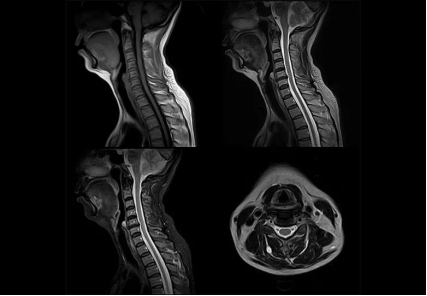

磁共振圖像舉例

核磁共振MRI

原理簡介:MRI的工作原理是讓共振人體的氫離子產(chǎn)生共振來產(chǎn)生圖像。我們?nèi)梭w有很多H2O,也就是水!所以,有水的地方氫離子多,反之則少,也就是說有水的地方核磁共振做得清楚,沒水的地方就做得不清楚。因此人們也戲稱它是搖一搖再看的檢查。

應(yīng)用:擅長檢查軟組織

優(yōu)點:輻射很小,沒有骨性偽影,能多方面、多參數(shù)成像,有高度的軟組織分辨能力;

缺點:檢查時間長,費用相對高;